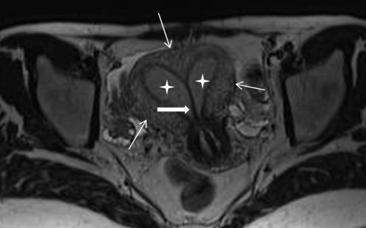

比如佳佳,而从核磁结果上看,子宫就变成了一个Y形,左右两边的宫腔都太小了。

我们的建议是,术前做个核磁共振检查,评估隔的大小,以及宫腔的大小。

而在红房子,我们制定了子宫纵隔矫形的手术标准,对于每一例子宫纵隔的患者,常规术前运用核磁共振检查,精确确定子宫外形、宫底形状,精准测量纵隔各个径线的大小,制定了每个人应该切除的范围。